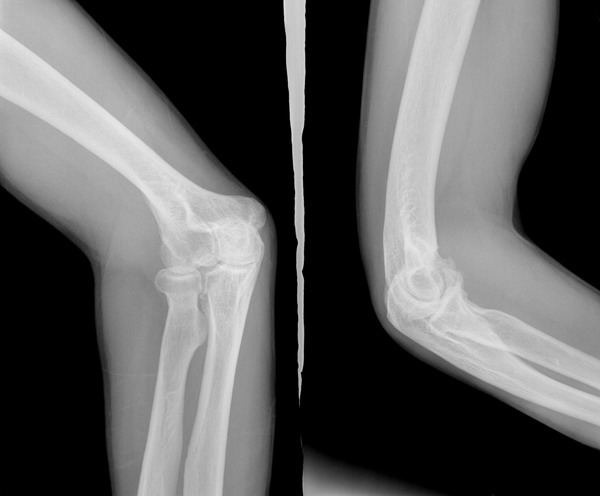

标题: X0830:这个肘关节是否正常?

男,43岁,外伤病人!

两幅图象拍的体位都不是很正,只见骨皮质不光整,但关节关系不好说。

正位不标准还是就是这样畸形。

好象肱骨滑车有点问题,片子位置不大好.

我又看了一下,尺骨冠突骨皮质不大连续,可能有骨折.

肱骨远端似有骨折。建议必要时mri。

考虑尺骨冠状突骨折可能,不完全除外滑车骨折。请重拍正位片

提携角过大 即使体位不正也不会过大

侧位片尺骨冠突处似见游离骨块,撕脱性骨折?